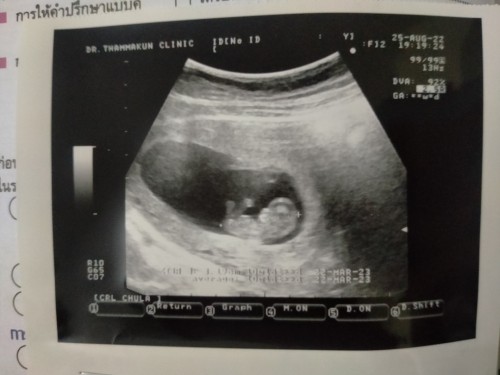

น้องตอน 9วีคค่ะ มีดิ้นทักทายขยับแขนขาขึ้นลงเบาๆ พรุ่งนี้จะซาว 10วีค เป็นกำลังใจและยินดีกับแม่ๆทุกท่านนะคะ ☺️🫶🏻🎊

ซาวด์ตอน10วีคตรงเรยจ้าแม่ ดูตัวน้องสิ เขาดูกันอย่างใงน้อ เห้นมีขาแขนแล้ว